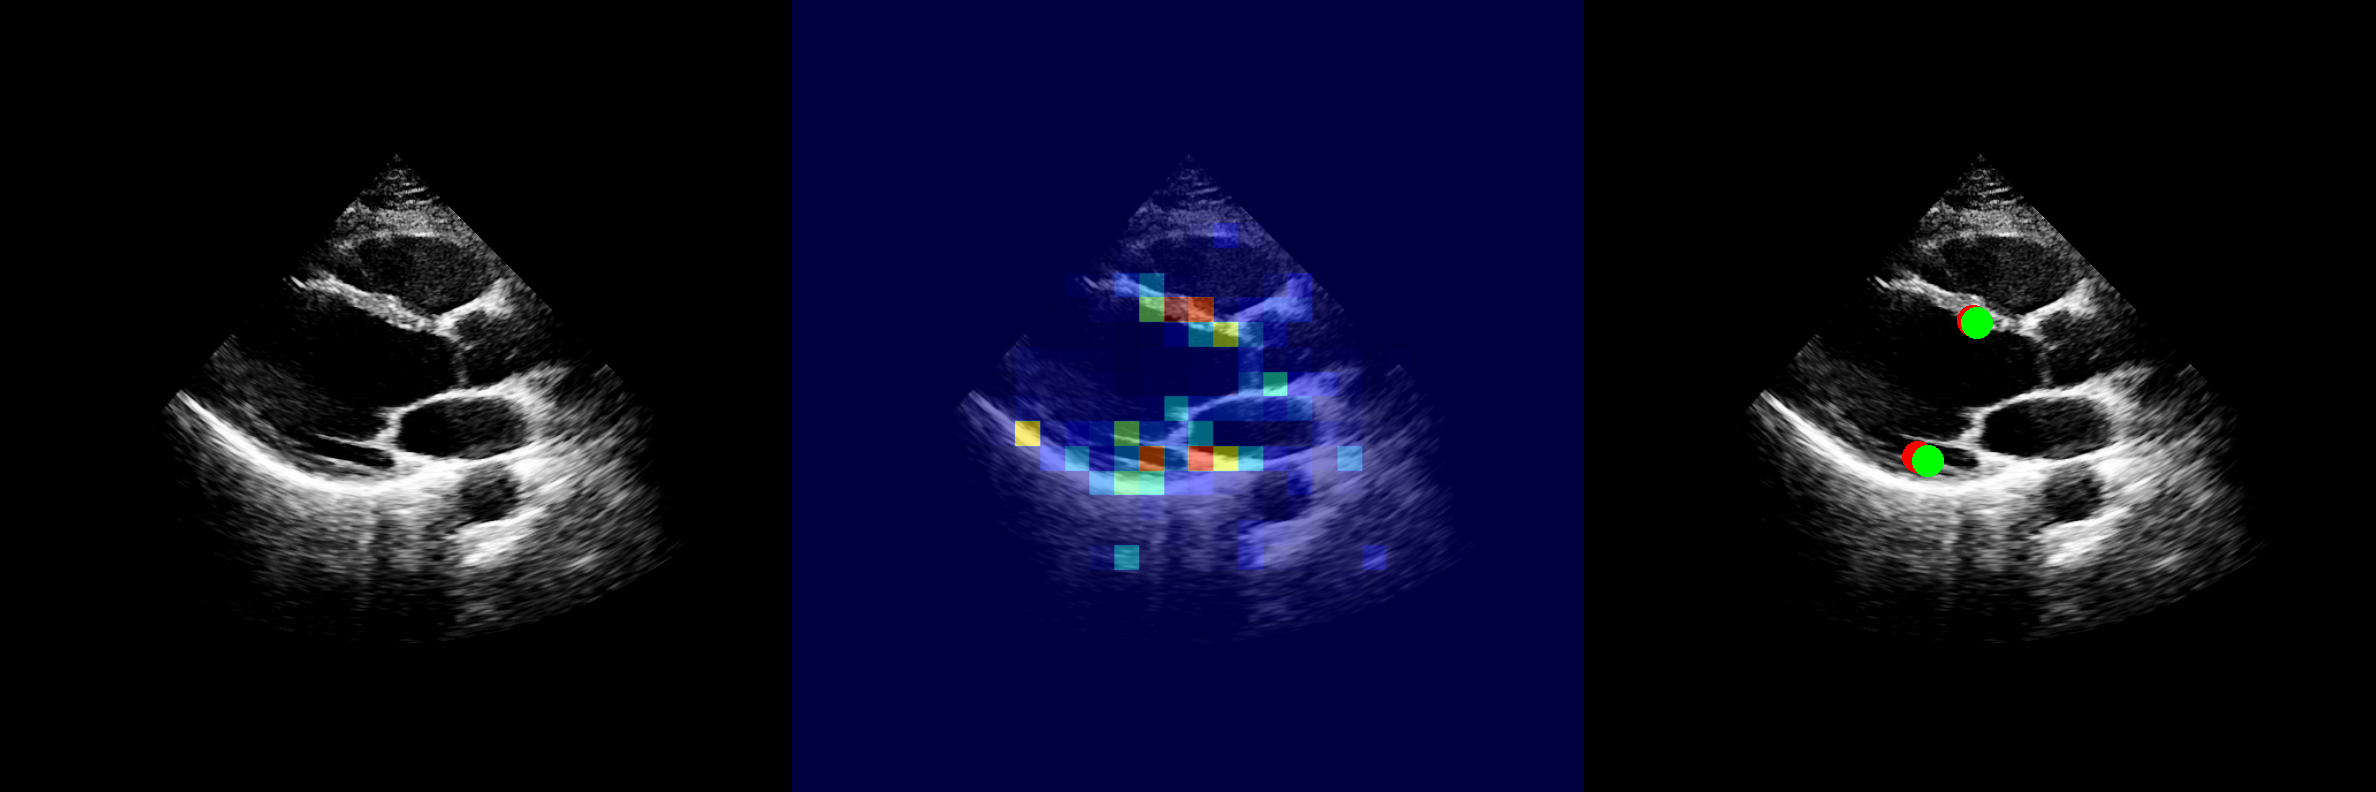

2.3 Interactive Structure Segmentation

We sought to evaluate EchoApex’s effectiveness in structure segmentation, a common yet time-consuming task in echo exams. We use three large public echocardiogram segmentation datasets, CAMUS [Leclerc2019DeepLF], EchoNet-Dynamic (ENDym) [Ouyang2020VideobasedAF], EchoNet-Pediatric (ENPed) [Reddy2023VideoBasedDL], as well as an internal dataset acquired with volume transducers. CAMUS includes left ventricle and left atrium tracings over an entire cardiac cycle. EchoNet-Dynamic provides tracings of the left ventricle in the apical-4-chamber (A4C) view at end-systole and end-diastole. EchoNet-Pediatric offers tracings of the left ventricle in both A4C and parasternal short axis (PSAX) views. The internal dataset comprises tracings of all four chambers, with biplanes utilized for training and evaluation. The number of annotations per dataset is shown in Fig. 4. We used the Dice Similarity Coefficient as our primary evaluation metric, consistent with the public benchmark. Additional details regarding the datasets, experimental setup, and other performance metrics are provided in Methods and Supplementary Table 9.

We build an interactive segmentation model EchoApex-SAM-B (and its variation EchoApex-SAM-S) by incorporating the pretrained EchoApex encoder and prompt-based (including points, box, and text) encoder-decoder modules following SAM [kirillov2023segment], the state-of-the-art foundation model on natural image segmentation. The model architecture is illustrated in Fig. 4. We compare EchoApex-SAM with two types of model. The first is MedSAM [ma2024segment], a foundation model trained on 1.5 million annotated images from diverse modalities, including CT, MRI, X-ray and ultrasound, and it is specialized in general medical image segmentation. The second are sub-task specialist models, e.g. a UNet model [Leclerc2019DeepLF], that are individually trained on and published together with each dataset. Results are illustrated in Fig. 4. We observe that the UNet specialist models generally shows better performance than MedSAM. This hints that adding additional data from different modalities does not necessarily improve the performance of the model on echo segmentation. As echo represents only a small portion (approximately 5%) of the training data in MedSAM, its model performance on echo may be impacted negatively by the imbalanced data distribution. We also observe that EchoApex-SAM-B outperforms both MedSAM and UNet-specialist on all categories in all datasets, achieving an average dice score of 0.927 (95% CI 0.926-0.928), showing an average of 0.23 and 0.57 dice improvement accordingly. This supports the observation that the model pretrained with more in-domain data will boost the performance on the target task.

2.3.2 Segmentation performance generalizability

We also assess the generalizability of the segmentation performance, i.e. how well it performs on unseen data. We retrain EchoApex-SAM from scratch on the EchoNet-Dynamic dataset, and compare its performance with the specialist model DeepLabV3 published together with the dataset. We used the ViT-S model to ensure a comparable model size with DeepLabV3. Following Fig. 4, We observe that EchoApex-SAM shows improved performance compared to DeepLabV3, not only on the in-domain test set from EchoNet-Dynamic, but also on the generalization test set. Specifically, EchoApex-SAM-S achieves an average dice score of 0.923 (95% CI 0.922-0.925) on the in-domain test set, and an average dice score 0.877 (95% CI 0.873-0.880) on the generalization test set, with 0.756, 0.905, 0.889 on Vol-Biplane, CAMUS and EchoNet-Pediatric respectively. The DeepLabV3 model achieves an average dice score of 0.915 (95% CI 0.913-0.917) on the in-domain test set, and an average dice score 0.834 (95% CI 0.829-0.840) on the generalization test set, with 0.744, 0.848, 0.844 on Vol-Biplane, CAMUS and EchoNet-Pediatric respectively. This indicates that the model pretrained on in-domain data, even after fine-tuned, can still be more robust and generalizable than the specialist models.